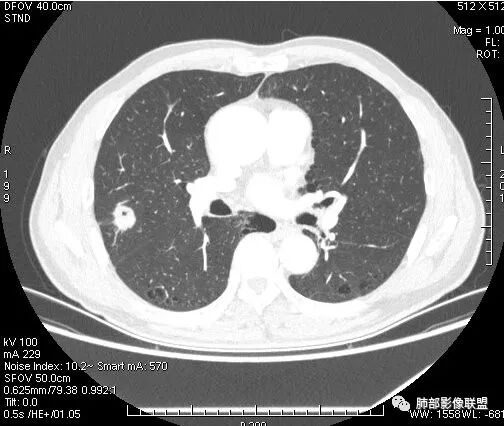

晨读:双肺胸膜下多发小气囊,大小不一,右肺结节,内部可见小空洞,洞壁光滑,厚薄不一,偏心性生长,近段血管束增粗,有分叶,毛刺(软),有晕征,平扫密度尚可,增强后不均匀强化,可见低密度坏死,及部分血管穿行,体检发现,考虑恶性:腺癌,鉴别炎性结节

右上叶结节,轻分叶,结节有长短不一毛刺,结节周围GGO边界清,有血管集束征,肺窗结节周围似可见卫星灶,可见鬼脸征,良恶性征象都有,但GGO边界清,浸润性腺癌耍考虑,临床症状轻微,体捡发现,似可见卫星灶和鬼脸征,炎性肉芽肿TB或隐球菌要鉴别。

虽然良恶性征象都有,但是这个病灶增强后坏死比较明显,如果是恶性:腺癌这样大小的结节坏死很少见,只有低分化腺癌可以坏死,但是低分化腺癌这种大小一般会有周围转移表现(叶间胸膜结节,癌淋或者淋巴结明显肿大),如果是鳞癌,收缩力,坏死情况以及没有支气管截断都不太支持,而且结节远端有几个小结节样改变,大家可能认为是血管,但我觉得应该是卫星灶。所以觉得隐球可能较大。壁胸膜的牵拉线也没有引起胸膜凹陷,比较纤细,至于病理中的丝状物不一定是真菌菌丝。

这个病例确实有很多隐球菌的特点,包括周围的卫星灶、周围的毛刺,它没有粗短的毛刺,它是稍长一点、柔弱一点的。我是觉得这个符合脐凹征,所以我觉得恶性不能排除,结果错了,是炎性。

这个大部分边缘稍微偏平直一点,血管走行非常自然,包括里面的空泡征样的,影子很干净,边界很光滑,都是些炎性特点。

6.灶周见小结节影(卫星灶),边界不甚清晰。

会是肿瘤吗?

1.病灶整体太圆,没有深分叶,没有粗短毛刺,收缩明显乏力,强化不显著等等缺乏典型肺腺癌的影像学特征。腺癌如此小病灶出现空洞更是匪夷所思!

2.肺鳞癌易坏死,可病灶如此小即出现影像学上可见的彻底的坏死空洞也非常少见。

会是感染吗?

病灶相对局限,或偏安肺野一隅,小病灶带空洞,最常见的还是感染。

1.结核是常见的,坏死也够彻底,有卫星灶。疑问在于血管为什么不受累?

2.其他的慢性炎症。边界清楚符合慢性。慢性肺脓肿、隐球菌感染、奴卡菌感染等等都可以。可惜缺乏病原学依据。